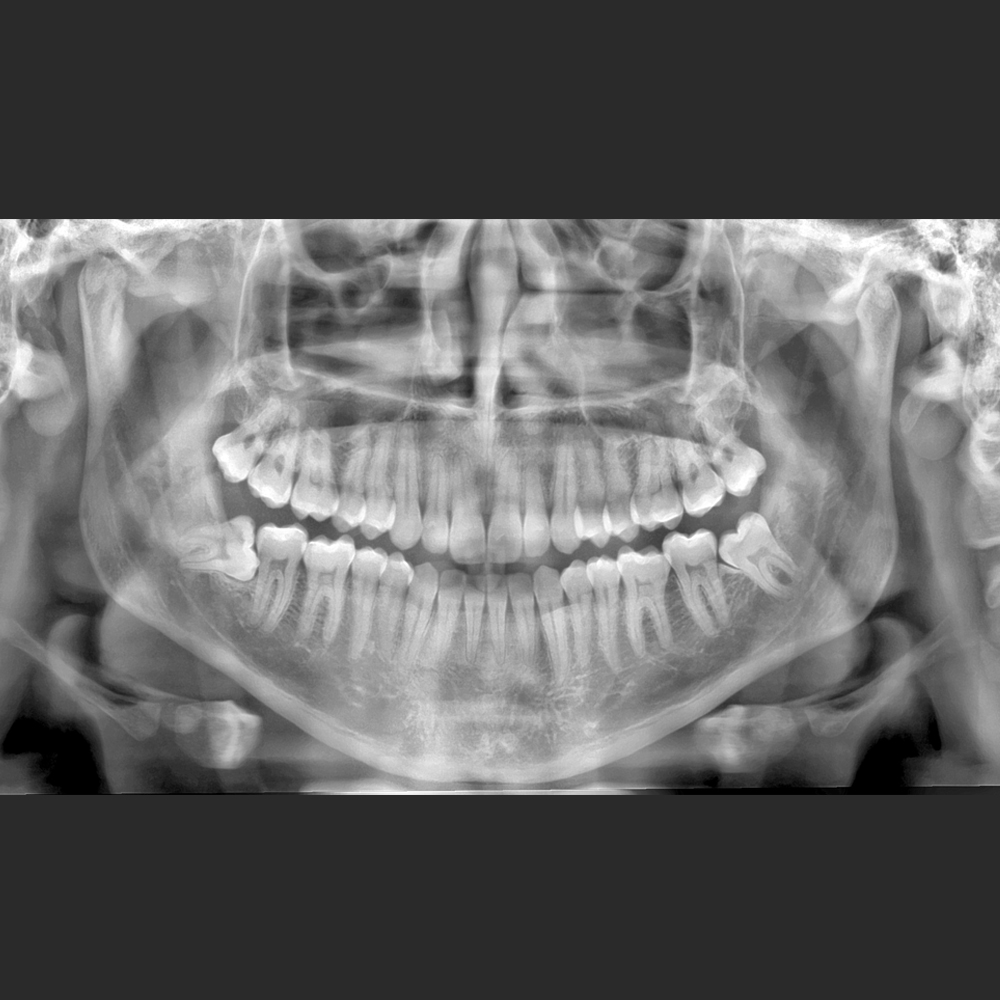

El Eagle 2D Pan/Ceph ofrece todos los exámenes en el perfil panorámico

(panorámica estándar, senos maxilares, baja dosis, bitewing, ATM, ortogonalidad perfeccionada, panorámica infantil y bitewing ortogonalidad perfeccionada)

Eagle Smart Contrast®

El algoritmo Eagle Smart Contrast® es una herramienta innovadora que actúa en todas las regiones de la imagen, tratando y perfeccionando el contraste de cada área individualmente. El resultado es uns imagen homopgénea y sin ruido, permitiendo la visualización de detalles y consecuentemente un mejor diagnóstico.